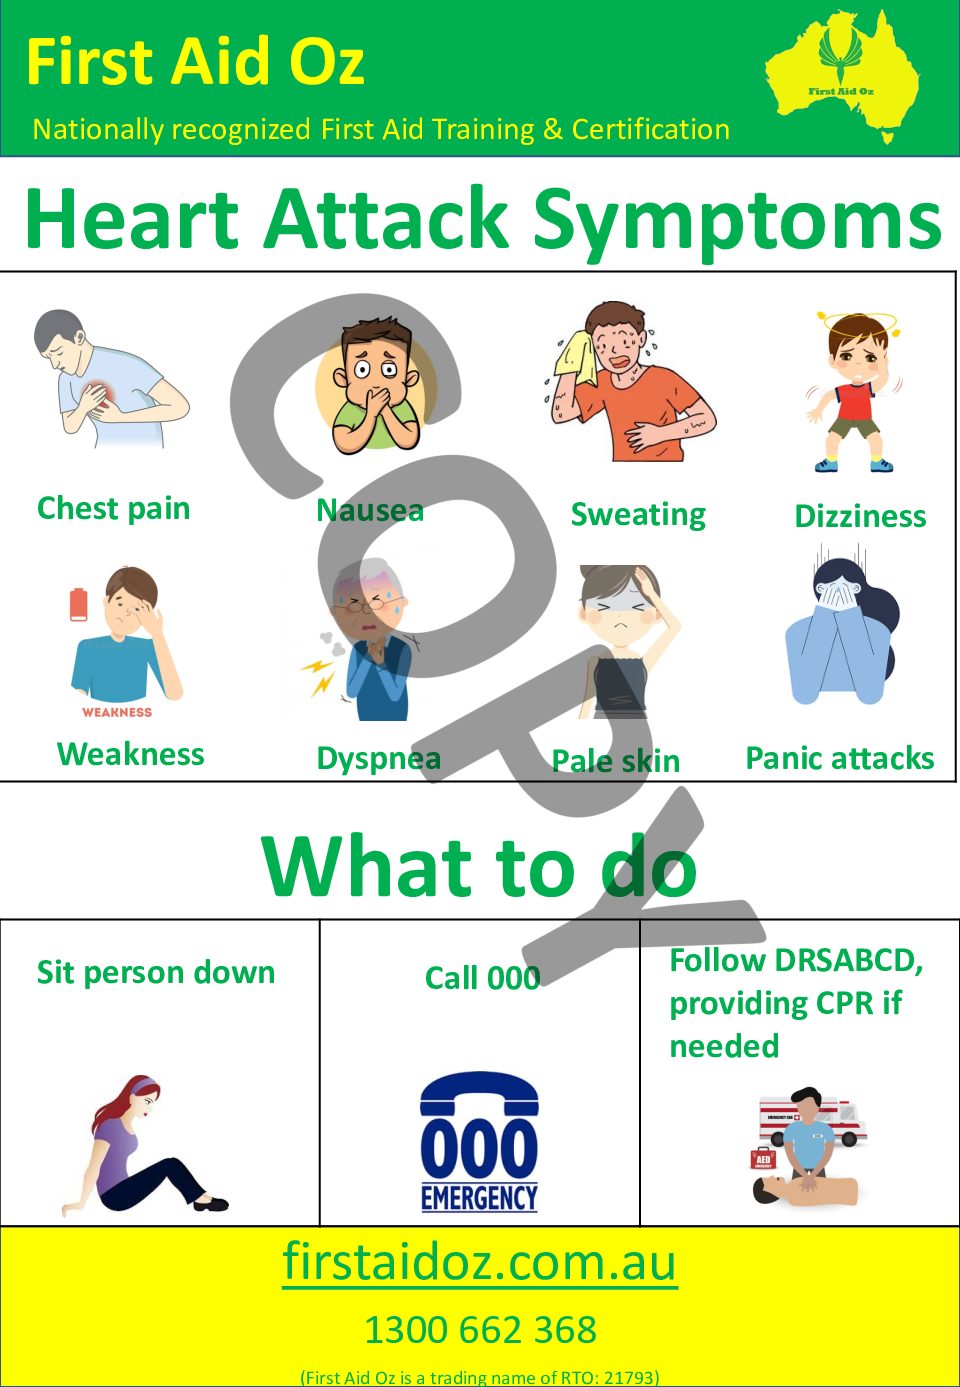

Heart Attack Poster First Aid Oz

Heart Attack Poster First Aid Oz